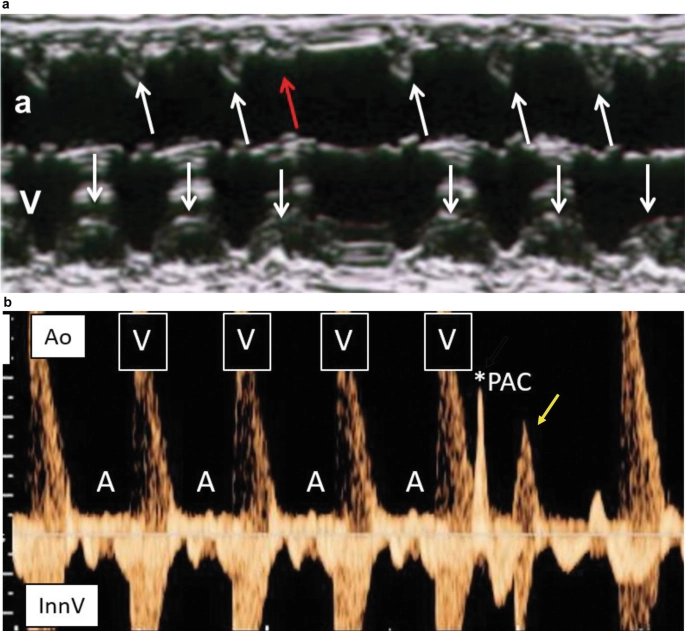

• Ngoại tâm thu

• Rối loạn nhịp nhanh

• Rối loạn nhịp chậm